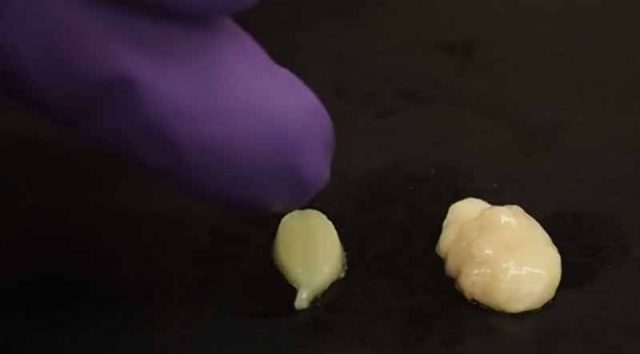

Meregenerasi Jaringan Lunak dengan Hidrogel

Para peneliti telah mengembangkan sejenis gel yang dapat menumbuhkan jaringan lunak baru atau menggantikan jaringan yang telah hilang, misalnya seperti otot, lemak, dan saraf. Dalam makalah yang telah diterbitkan di jurnal Science Translational Medicine, tim peneliti yang berasal dari Johns Hopkins School of Medicine, mendeskripsikan upaya mereka dalam mengembangkan sejenis gel, dan seberapa besar manfaatnya melalui pengujian yang dilakukan terhadap tikus dan...